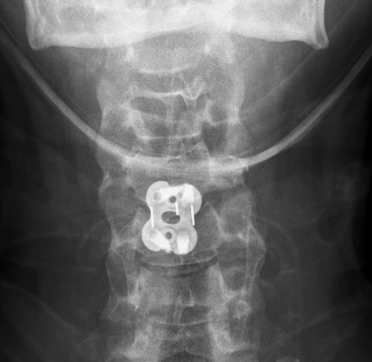

Xray / CT

Usually thin fracture fragment

Widening of disc anteriorly

Stages

1. Anterior ligament failure

– disc space widening (or transverse fracture of vertebral body)

2. Posterior ligament failure

- retrolisthesis of superior vertebral body

Management

Anterior +/- posterior approach